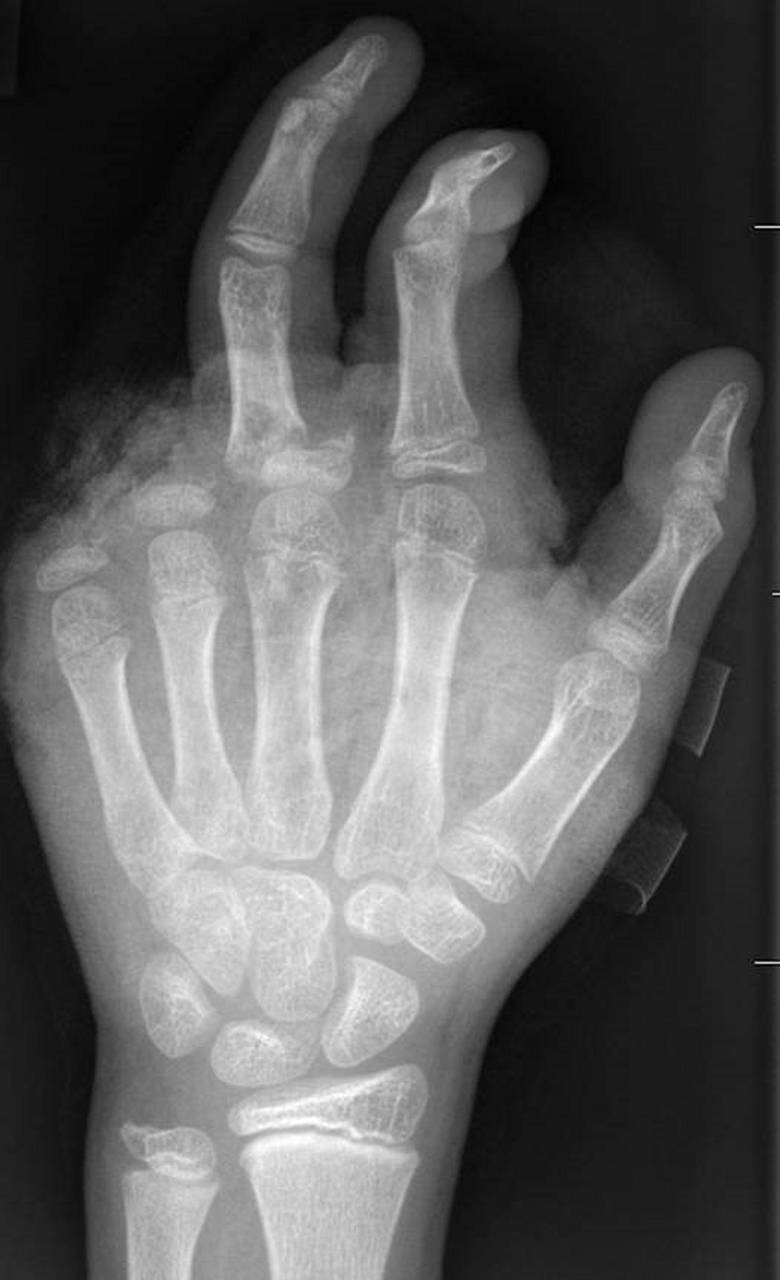

So kann ein Röntgenbild nach einer missglückten Böllerexplosion aussehen: Zwei Finger fehlen. © -/UKB/dpa

So kann ein Röntgenbild nach einer missglückten Böllerexplosion aussehen: Zwei Finger fehlen.